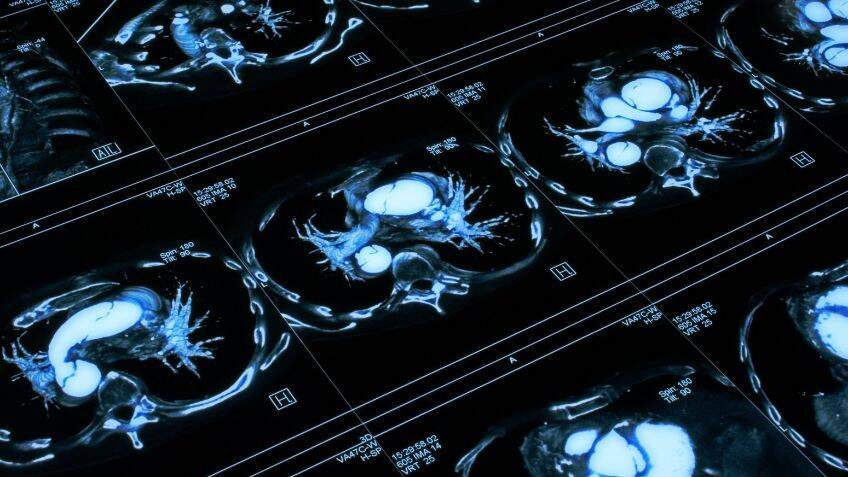

Can MRI scans detect a rare heart disease? By wpengine 30th May 2025 Researchers found that MRI scans could help to spot this typically undiagnosed condition This content is for members only. Please click here to view the full article.